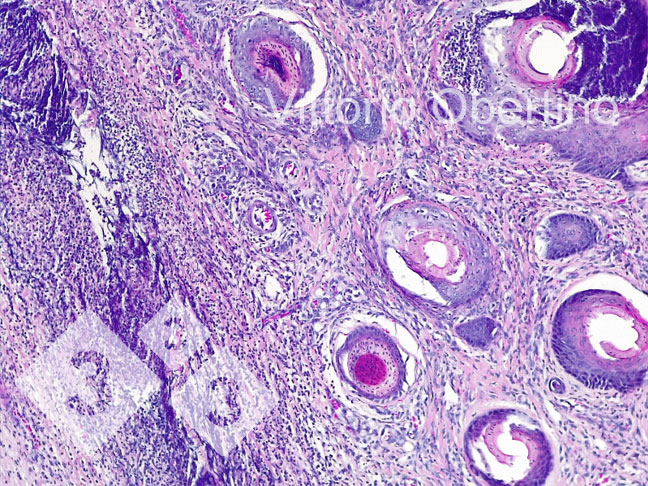

2- Des échantillons de tissus ont été envoyés à l'Université de Turin pour vérifier que les lésions étaient histologiquement compatibles avec les images décrites dans la littérature (Kuehling et al. 2020).

Figure 9. Peau. Érosion épithéliale focale dans laquelle la couche superficielle est remplacée par un matériel éosinophile amorphe à granulaire abondant avec des débris cariorectiques (nécrose) et des granulocytes neutrophiles dégénérés et viables abondants. Multifocalement, l'épithélium apparaît modérément à fortement hyperplasique avec une hyperkératose orthokératosique modérée à sévère. Il existe également une présence multifocale de croûtes. Le derme apparaît diffus et modérément fibreux.